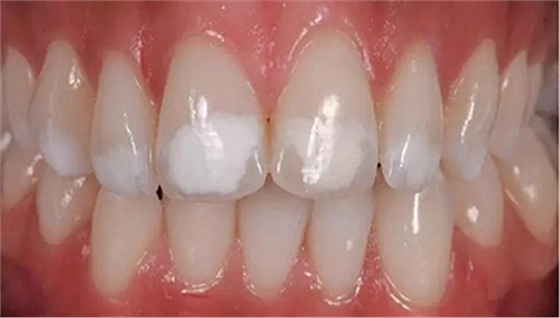

一28歲女性患者來我院修復(fù)科就診,主訴為前牙嚴(yán)重的牙齒著色和缺損十余年,要求改善牙齒的美觀。臨床檢查表明該患者有重度氟斑牙,極大的影響了前牙美學(xué)。

考慮到患者為年輕人,保守治療方法比傳統(tǒng)侵入性治療手段更為合適。術(shù)前牙周治療預(yù)防牙齦炎癥和改善牙齦健康狀態(tài),隨后聯(lián)合采用釉質(zhì)打磨、牙漂白和樹脂滲透來處理牙釉質(zhì)表面。

1、利用高速渦輪機(jī)配105 um金剛砂車針磨除200-400 um的牙釉質(zhì)。